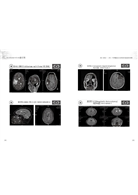

例如美國精神科醫師就問林慶恆醫師:「報告中所謂:利用SPECT-CT對針灸手三里穴位,對人體腦血流的影響,這項研究有做過大規模的統計嗎?」

李于一(NANA LEE)博士即在聽了林醫師的說明後,回答:「此為受試者自己跟自己比較,並分析針灸前、後的腦血流灌注情況之改變,並長期觀察、紀錄的結果。」說明此為中西醫結合研究的成果之一,與傳統中醫學臨床的研究方向不同。與會人士對於類似的說明都表示理解與認同。

‧利用SPECT醫學影像技術—觀察針灸手三里後腦血流變化…林慶恆中醫師 232

Using SPECT Medical Imaging Technology to Observe Changes in Cerebral Blood Flow

After Acupuncture and Moxibustion at the Shousanli Acupoint— Lin Ching-Heng